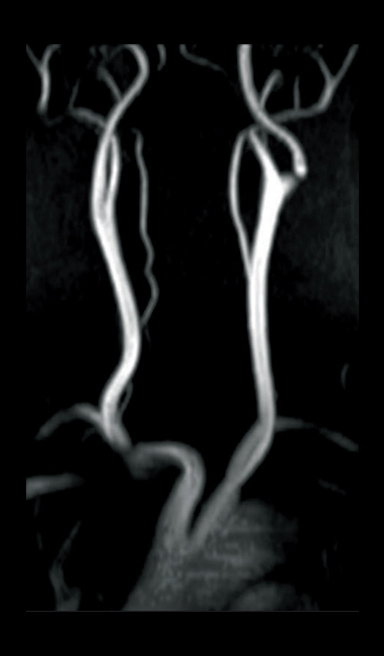

Respiratory-gated MIP image